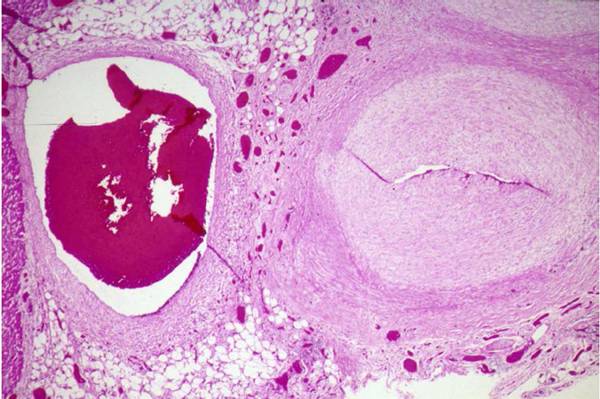

川崎病血管病变主要累及肌性动脉,并以坏死性动脉炎、亚急性/慢性血管炎、血管内肌纤维母细胞增生(LMP)为特征病变。

大型或巨型冠状动脉瘤的直径≥8 mm或Z评分≥10时,不需处理,它们很少破裂,一般含有血栓,易致血管堵塞。动脉瘤明显受损但部分血管中层保留的情况下,随着时间延长,其直径可能因LMP和血栓而减小,并逐渐狭窄。

亚急性/慢性炎症引发的心包炎和心肌炎常出现在冠脉周围,但川崎病即使在晚期,也不会出现动脉粥样硬化性特征。

图1. 一名19个月川崎病婴儿的心外膜冠状动脉(右)和心外膜静脉(左),该幼儿患病10个月后死亡。